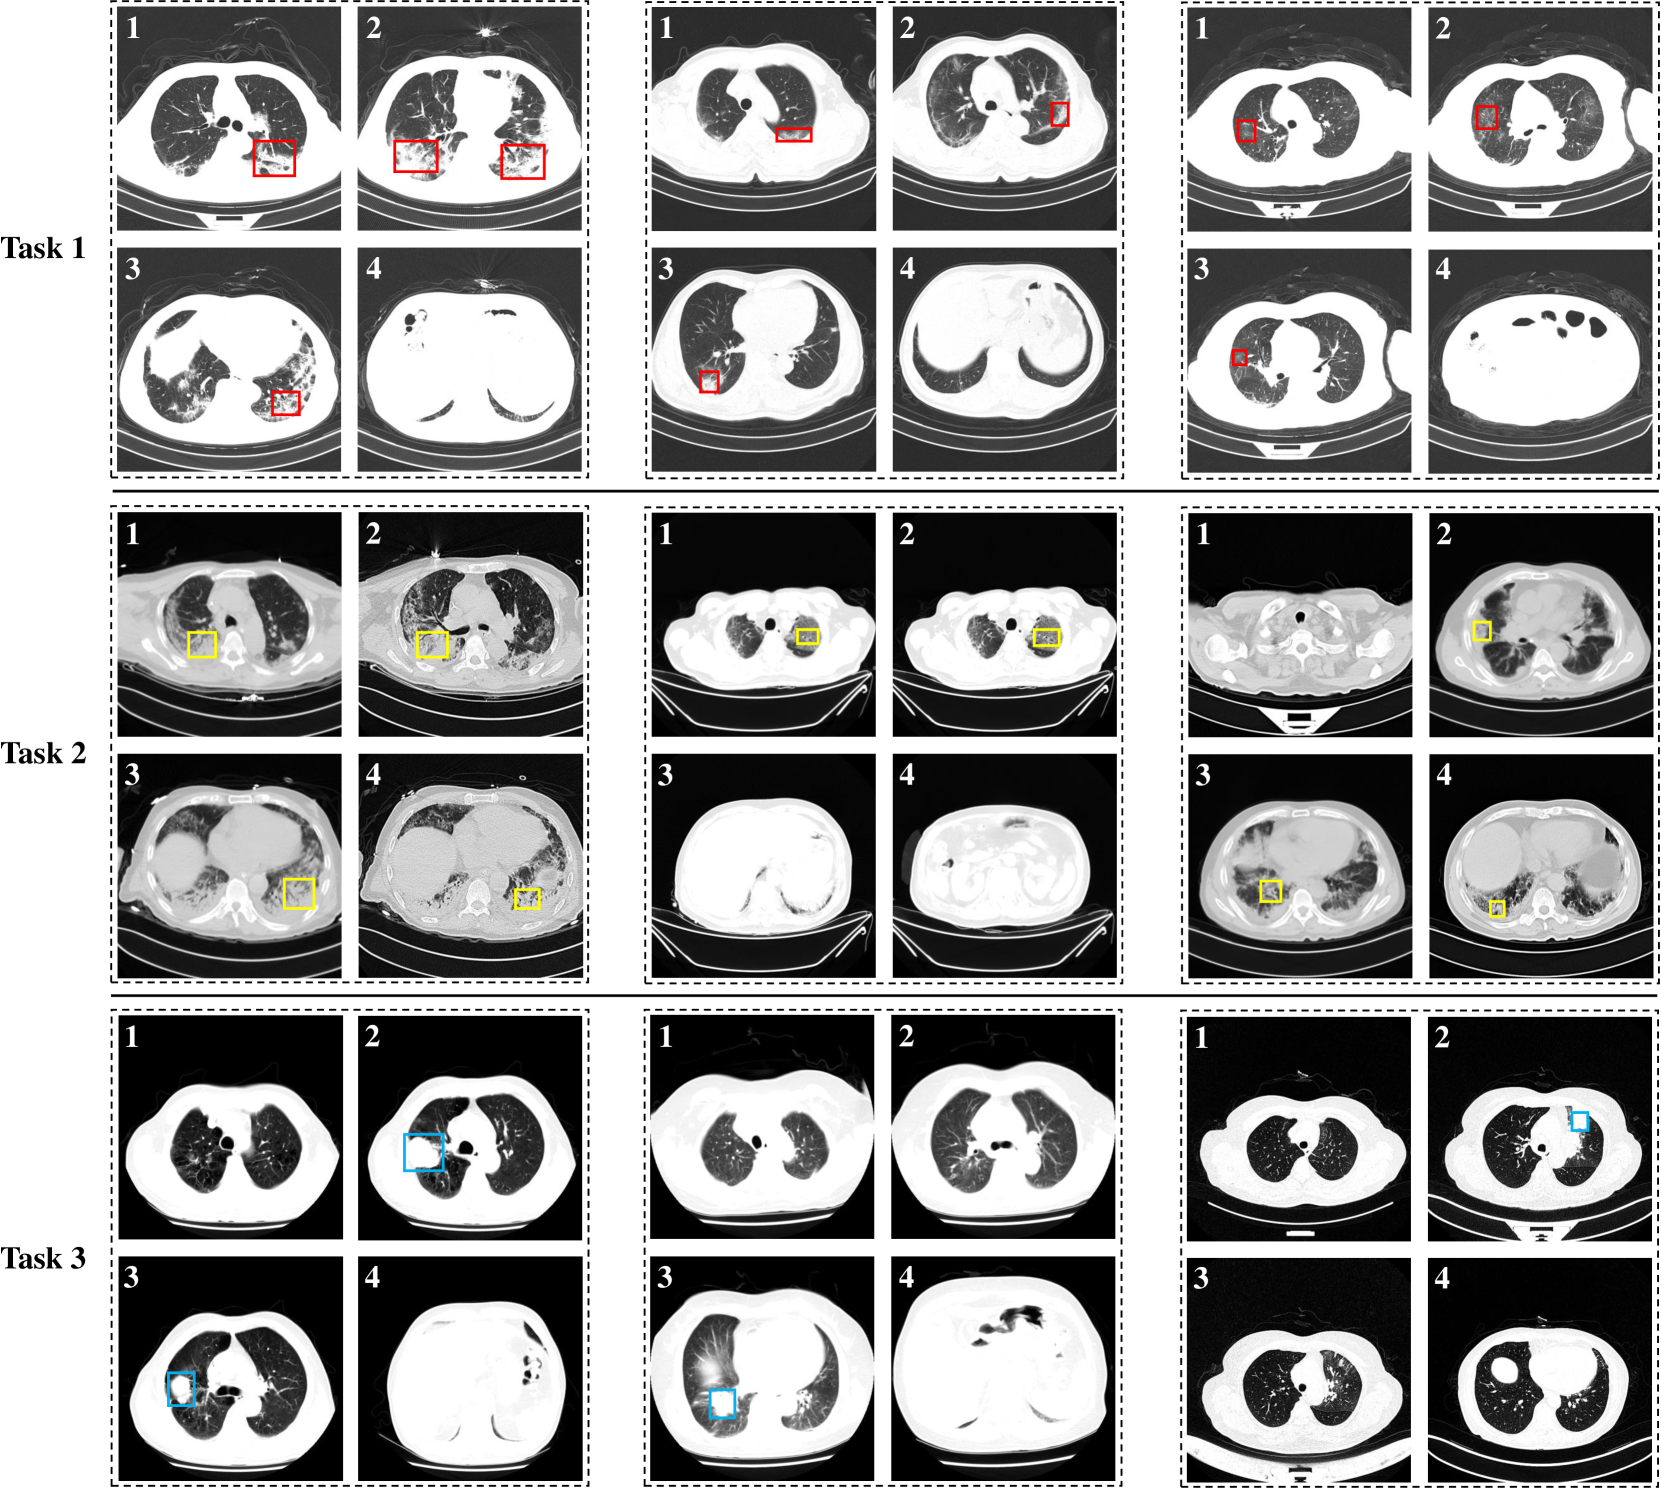

Refer to caption

Figure 4: Visualization of CT slices selected by our proposed CSS. The red, yellow and blue boxes mark the lesion areas of NCP, CP and AC, respectively.

We visualize the slices selected by our proposed CSS method, as shown in Fig. 4. In Fig. 4, rows 1, 2, and 3 show the selected CT slices in Task 1, 2 and 3, respectively. Each task displays three cases, with each case retaining four slices. From Fig. 4, we have several observations: (1) the slices selected by our proposed CSS contain lesion areas, indicating that the CSS method can select representative slices to aid in diagnosis; (2) In Task 1 and Task 2, the number of slices with lesions is significantly greater than that in Task 3. For example, in Task 3, only one slice in the second and third cases has AC. This shows that in the entire CT volume, the number of slices indicating AC may be less than those indicating pneumonia. In other words, AC is less obvious on CT and more difficult to diagnose, which is consistent with the experimental results in Section 4.3.